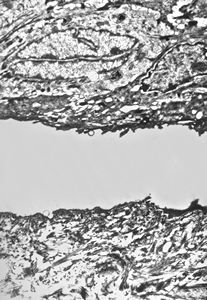

F, 1y. | epidermolysis bullosa … dystrophic form

M, 22y. | epidermolysis bullosa - junctional type

M, 22y. | epidermolysis bullosa - junctional type, uncompletely separated basement membrane

M, 1y. | epidermolysis bullosa … junctional type

M, 1y. | epidermolysis bullosa … junctional type

F, 41y. | epidermolysis bullosa … dystrophic type

F, 41y. | epidermolysis bullosa … dystrophic type

F, 41y. | epidermolysis bullosa … dystrophic type

M, 1y. | epidermolysis bullosa … junctional type … rudimentary hemidesmosomes, missing anchoring fibrils

M, 1y. | epidermolysis bullosa … junctional type … rudimentary hemidesmosomes, missing anchoring fibrils

M, 1y. | epidermolysis bullosa … junctional type

M, 1y. | epidermolysis bullosa … junctional type

M, 1y. | epidermolysis bullosa … junctional type

M, 1y. | epidermolysis bullosa … junctional type

M, 1y. | epidermolysis bullosa … junctional type

F, 1y. | epidermolysis bullosa … dystrophic form